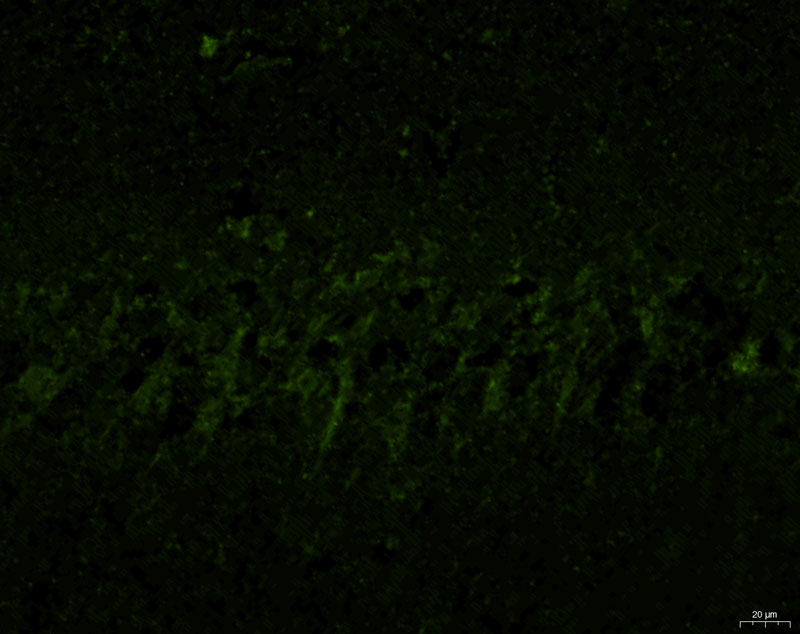

模型組1-2-40X-G